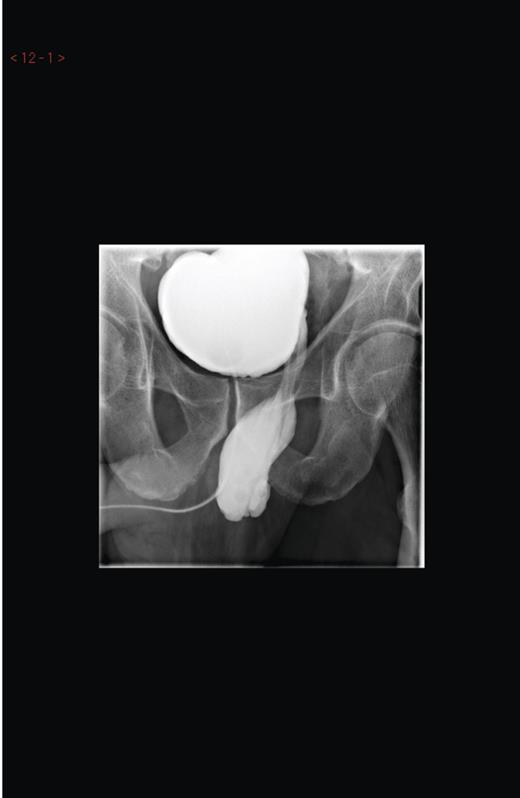

Based on this cystoscopic finding, a micturating cytogram was arranged to evaluate this diverticulum as seen in the figures provided (Figures 1 and 2). This showed an unusual huge bladder diverticulum that had herniated through his inguinal canal, filling his left hemiscrotum.

Micturating cystourethrogram showing contrast in the left hemiscrotum.